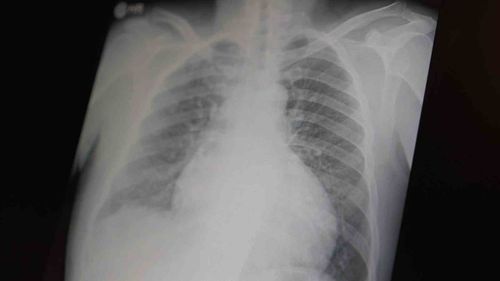

Prof. Dr. Şevket Özkaya: Metamfetamin ve kokain gençler arasında tehlike oluşturuyor Uzman uyarısı: Sentetik ve uyarıcı maddelerin gençlerde yarattığı sağlık riskleri Göğüs Hastalıkları Uzm. Prof. Dr. Şevket Özkaya, çocuk ve gençler arasında giderek artan bağımlılıklar olarak metamfetamin ve kokain üzerinde…